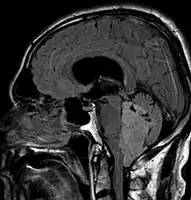

Morphology

Ependymomas are composed of cells with regular, round to oval nuclei. There is a variably dense fibrillary background. Tumor cells may form gland-like round or elongated structures that resemble the embryologic ependymal canal, with long, delicate processes extending into the lumen; more frequently present are perivascular pseudorosettes in which tumor cells are arranged around vessels with an intervening zone consisting of thin ependymal processes directed toward the wall of the vessel.[4]

It has been suggested that ependymomas are derived from radial glia, despite their name suggesting an ependymal origin.[5]